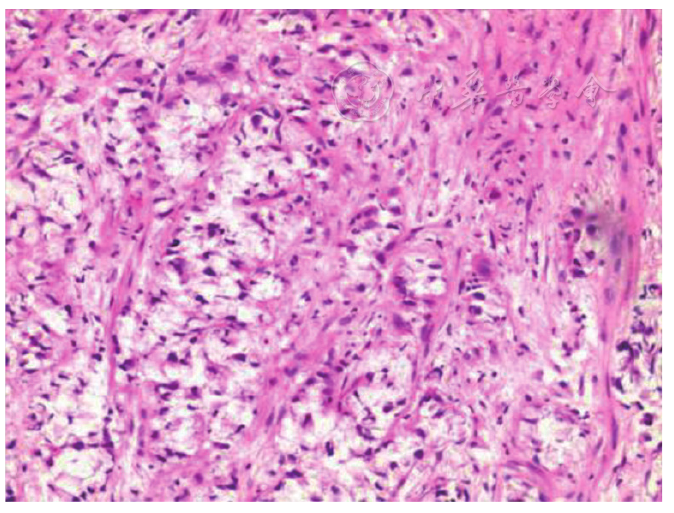

图1 胸部增强CT(2022年10月14日)。A、B:CT肺窗及纵隔窗提示左肺下叶类圆形肿块,边界清,边缘光整,相应支气管狭窄闭塞;C、D:增强扫描病灶明显不均匀强化,内见斑片状无强化坏死区;E:左侧胸膜多发结节状增厚(红色箭头),提示胸膜转移;F:左肺门见转移淋巴结(红色箭头),伴有坏死。CT:计算机断层扫描